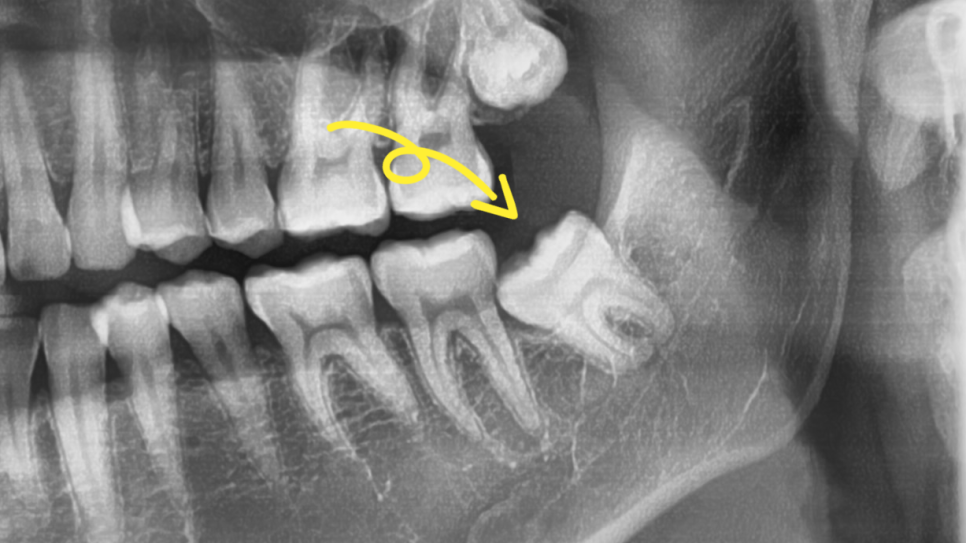

어떤 문제가 생긴 건지 파노라마 사진을 통해

현재 상황을 살펴봤더니

왼쪽 아래쪽에 위치한 부분 매복 형태의

어려운 사랑니가 눈에 띄네요.